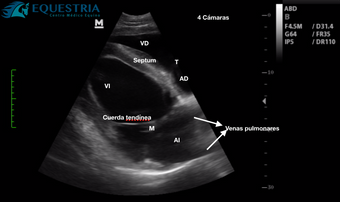

Imagenología: Radiología digital, ultrasonografía, video endoscopía.

Medicina interna: cuadros Digestivos, Respiratorios, Cardiovasculares, Neurológicos, Genito Urinarios, etc.